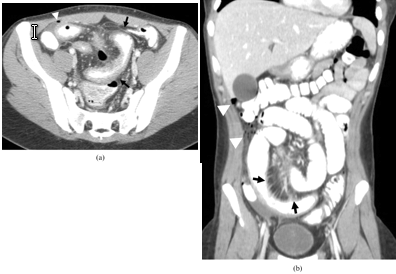

| Trước hoặc sau phẫu thuật: Sau cuộc phẫu thuật liên quan đến hệ tiêu hóa như cắt đoạn ruột, phần lớn bệnh nhân phải kiêng ăn rau từ 2 - 6 tuần để ruột có thời gian lành lại."Nói chung, chúng tôi khuyến cáo bệnh nhân tuân thủ chế độ ăn ít chất xơ để giảm lượng chất này đi qua ruột, sau đó mới yêu cầu họ quay trở lại chế độ ăn cũ để xem phản ứng", Rumsey giải thích. |